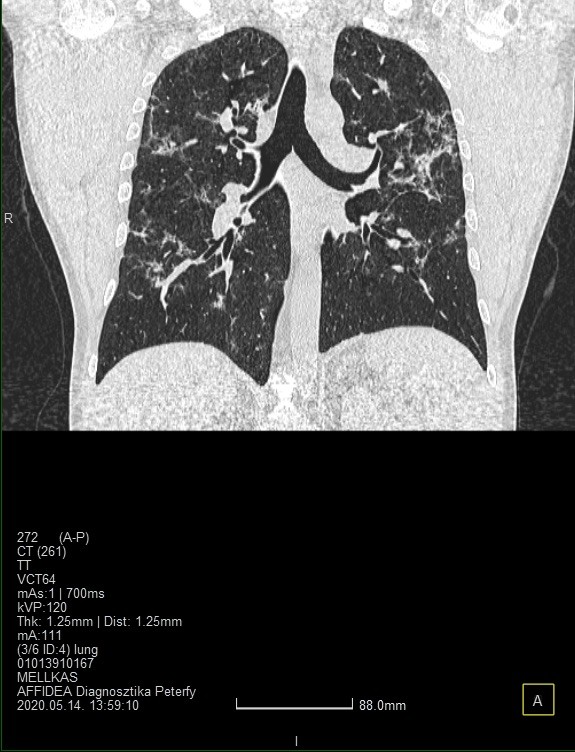

Koronavírusos magyar beteg tüdeje az 1. és a 18. napon

Forrás: Semmelweis Egyetem Orvosi Képalkotó Klinika

A körülírt homályos részek térbeli elhelyezkedése - kiterjedése megmutatja azt is, hogy mennyire súlyos a páciens állapota, illetve a következő napok klinikai prognózisára is következtetések vonhatók le.

A foltok általában először a tüdő jobb oldalán jelennek meg, a betegség súlyosbodásával pedig a tüdő mindkét oldalán megfigyelhetők lesznek, más gyulladásos elváltozások kíséretében. Az már nagyon súlyos állapotot feltételez, ha a gyulladás és a tejüveghomály foltok a tüdő 75 százalékát érintik, illetve mellkasi folyadék jelenik meg.”